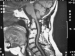

Die rheumatische Wirbelsäule Journal für Neurologie, Neurochirurgie und Psychiatrie 2014; 15 (2): 82-88 Volltext (PDF) Summary Praxisrelevanz Abbildungen Keywords: Halswirbelsäule, HWS, Neurochirurgie, operative Behandlung, Rheumatoide Arthritis, Wirbelsäule Rheumatische Erkrankungen sind meist chronisch verlaufende Störungen des Immunsystems, die mit Entzündungen unterschiedlicher Körpergewebe einhergehen. Die Prävalenz der rheumatoiden Arthritis in Deutschland ist ziemlich konstant und liegt zwischen 0,5 und 0,8 %. Sie manifestiert sich bevorzugt am Bewegungsapparat. Auch innere Organe wie Herz und Nieren können bei einer rheumatischen Erkrankung befallen sein. Nach den metatarsophalangealen Gelenken und den metacarpophalangealen Gelenken stellt die Halswirbelsäule (HWS) die dritthäufigste Lokalisation der rheumatoiden Arthritis dar. An der Wirbelsäule manifestiert sich die Erkrankung fast ausschließlich an der HWS. Als vorwiegendes Symptom findet man den Nackenschmerz. Ursache hierfür ist neben entzündlichen Gelenksveränderungen eine begleitende Instabilität. Erkrankungsfolgen an den Extremitäten erschweren die neurologische Untersuchung der Patienten. Auch begrenzen begleitende Polyneuropathien eine neurophysiologische Bewertung. An der Wirbelsäule ist die Therapie der Wahl die Stabilisierung betroffener Segmente, um durch Ruhigstellung Schmerzen zu reduzieren und instabilitätsbedingte Risiken für Querschnittslähmungen zu vermeiden. |